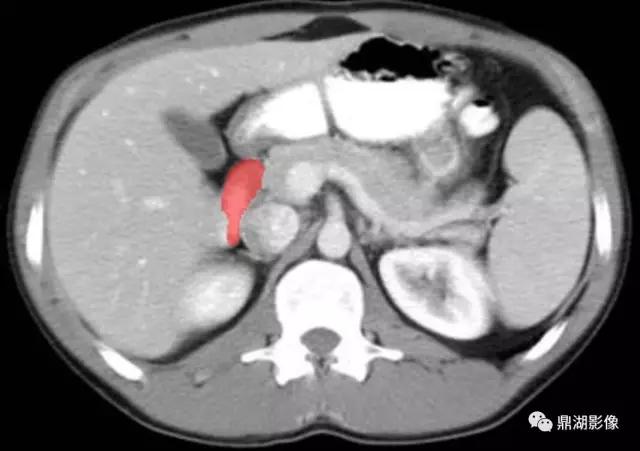

脾静脉(Splenic Vein)

肠系膜上静脉(Superior Mesenteric Vein)

膈肌脚(Curs of Diaphragm)

下腔(Inferior Vena Cava)

十二指肠(Second Portion of the Duodenum)

肠系膜上动脉(Superior Mesenteric Artery)